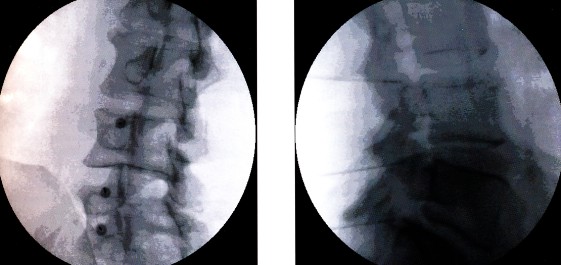

De anesthesioloog/pijnspecialist probeert aan de hand van een gesprek, lichamelijk onderzoek, en/of röntgenfoto’s te bekijken hoe hij uw pijn kan verminderen. Bij het eerste bezoek zal hij u adviseren over een behandelplan. U kan zelf beslissen of U dit wel of niet wil laten uitvoeren. Erna worden er eventuele verdere afspraken gemaakt.